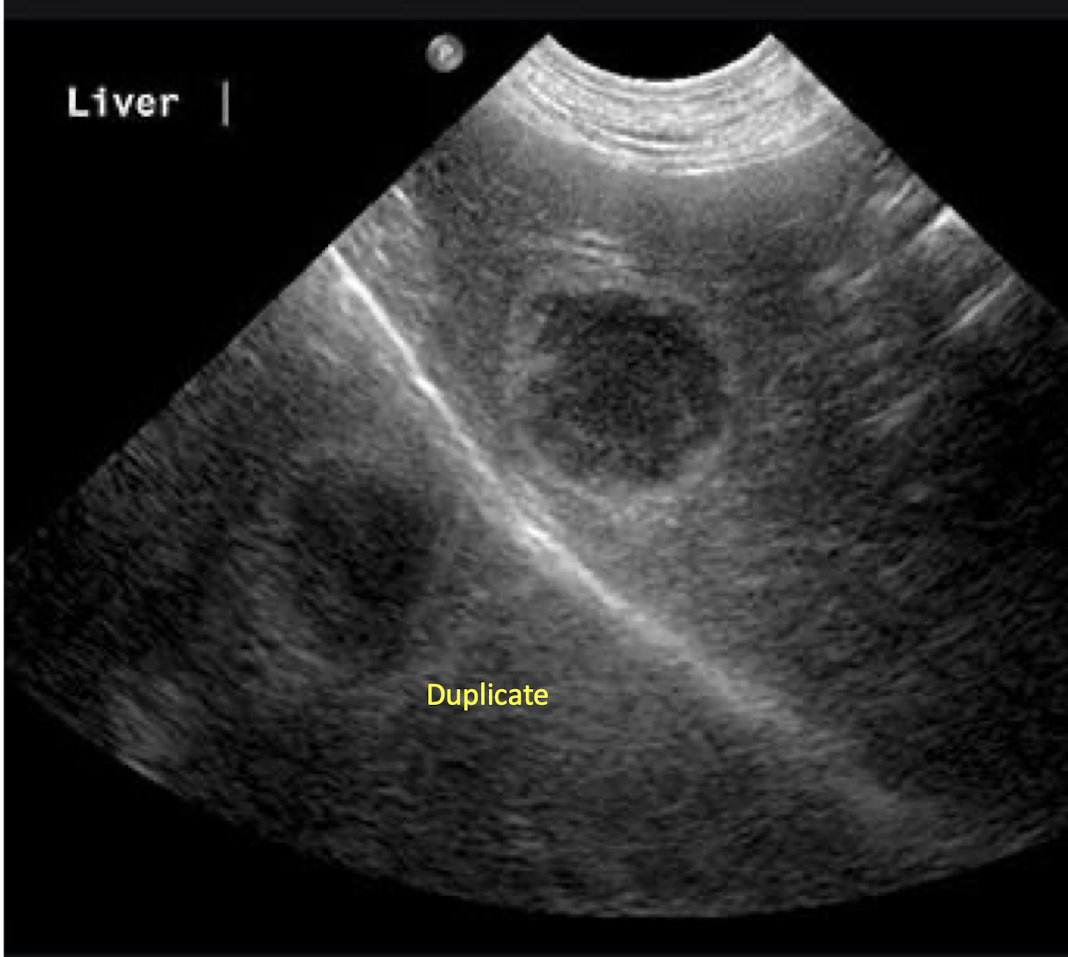

duplication of image of the opposite side of a strong reflector

mirror image artifact

What artifact is this showing?

Where is a mirror image artifact the most common to be found? What medium would be the strong reflector here?

thorax/abdomen interface; diaphragm